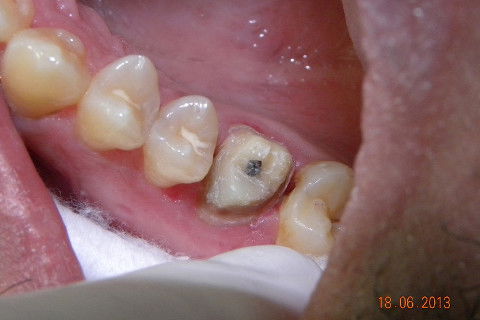

1ª CONSULTA: Instalação de pinos metálicos rosqueáveis

1ª CONSULTA: Núcleo de preenchimento em resina.

1ª CONSULTA: provisório direto, confeccionado no consultório, famosa técnica da "bolinha".

Caso de fratura de um trabalho protético preexistente, não sei qual e nem o paciente soube informar. Na minha opinião caso indicado para pinos metalicos rosqueáveis, muitos colegas condenam e indicam para esse caso pino metálico fundido. Creio que o fato de você fazer o preenchimento do núcleo com resina e depois cimentar com um cimento resinoso onde vai haver adesão química nas duas partes, formando um corpo único entre núcleo e coroa, ofereça uma resistência muito maior do que uma linha de cimentação onde a retenção é apenas mecânica. Continuando... 1ª CONSULTA: Pinos metálicos rosqueáveis, preenchimnto em resina, coroa provisória e moldagem com sil de adição (para qe possamos vazar o troquel e no mesmo molde o modelo para aplicação da cerâmica. 2ª CONSULTA: restauração de uma cárie no dente 17 (eu sei que era para ter feito na 1ª consulta por conta do ponto de contato, mas não deu tempo) e cimentação com cimento resinoso da 3M e caso encerrado. A radiografia não é desse caso, mas de uma caso igualzinho, a única diferença foi que envolveu cirurgia periodontal, veja como há a formação de um corpo único entre, núcleo e coroa. Um abraço. Jadson.